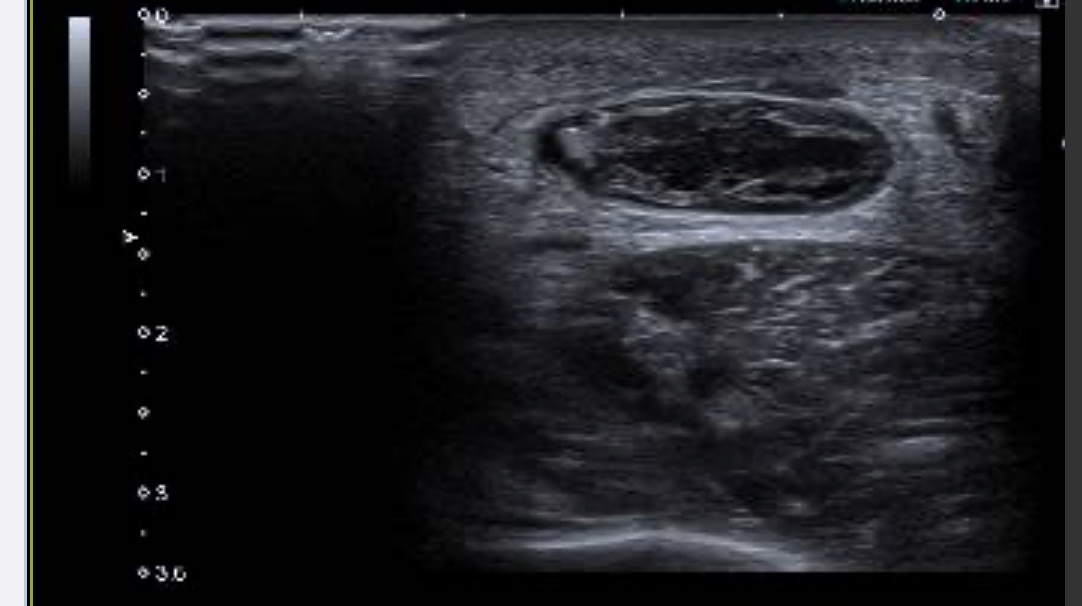

En la segunda imagen vemos en corte transversal una imagen con contenido hipoecogénico que corresponde con la zona de rotura tendinosa. Por último en la tercera imagen vemos la inserción tendinosa en el calcáneo conservada.